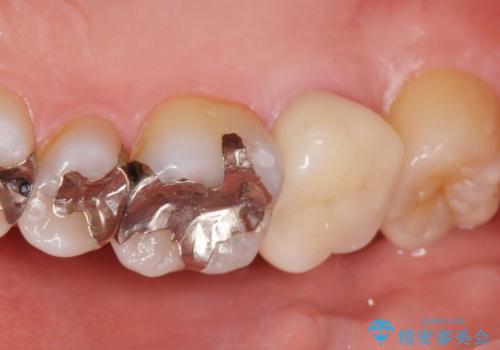

移植がうまくいかない可能性を考慮し、ブリッジもできるよう隣の親知らず(右上8)は残し、反対側の親知らず(左上8)を移植しました。

「状態の悪い銀歯がなくなりすっきりした」と喜んで下さいました。

見た目や使用感にご満足頂き、他の部位も現在治療中です。

クラウンの種類:オールセラミッククラウン ベレッツァ